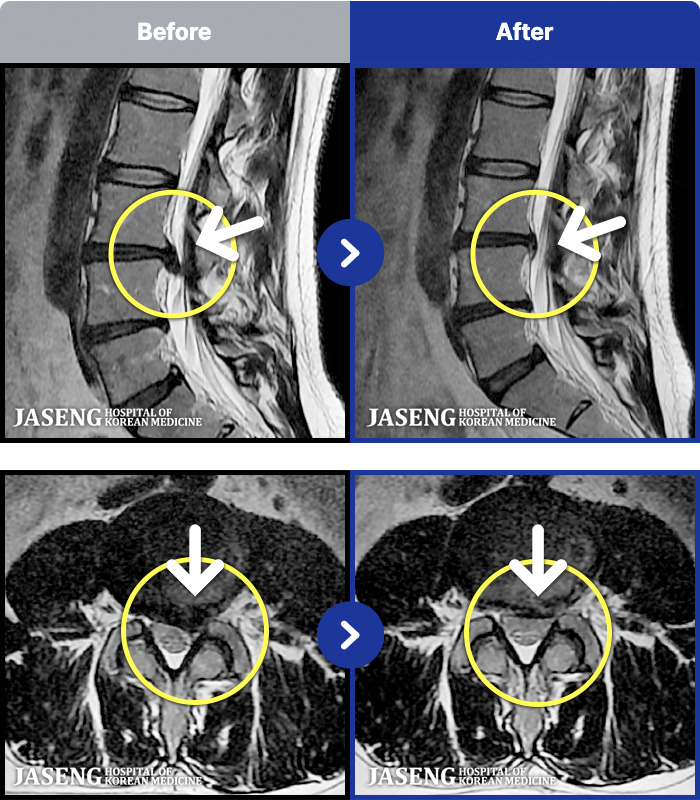

MRI ġ

MRI ũ ʸ Ȯϼ.